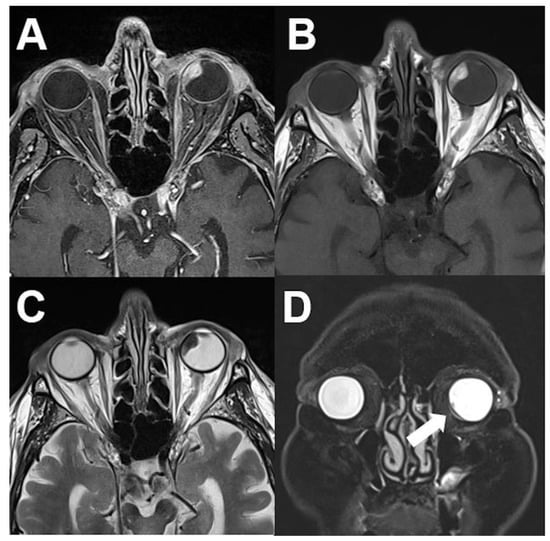

3.2. Intraconal Tumors

3.2.1. Venous Varices

3.2.2. Cavernous Hemangioma